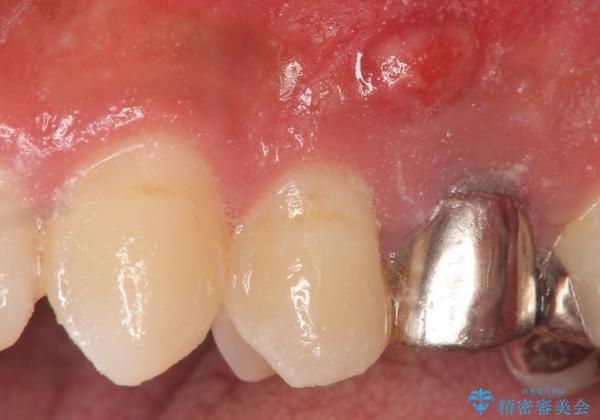

オールセラミッククラウン 歯茎にできた膿の出口(フィステル)の治療

- 歯茎にできものが出来てなかなか治らないので診て欲しいといらっしゃった方の症例です。

診査の結果、左上4番目の歯の神経が死んでおり、根尖に膿が溜まっていることが原因とわかりました。

そのため左上4番目の歯は根管治療を行い、歯茎の膿の出口の消失を確認後、オールセラミッククラウンによる補綴を行いました。